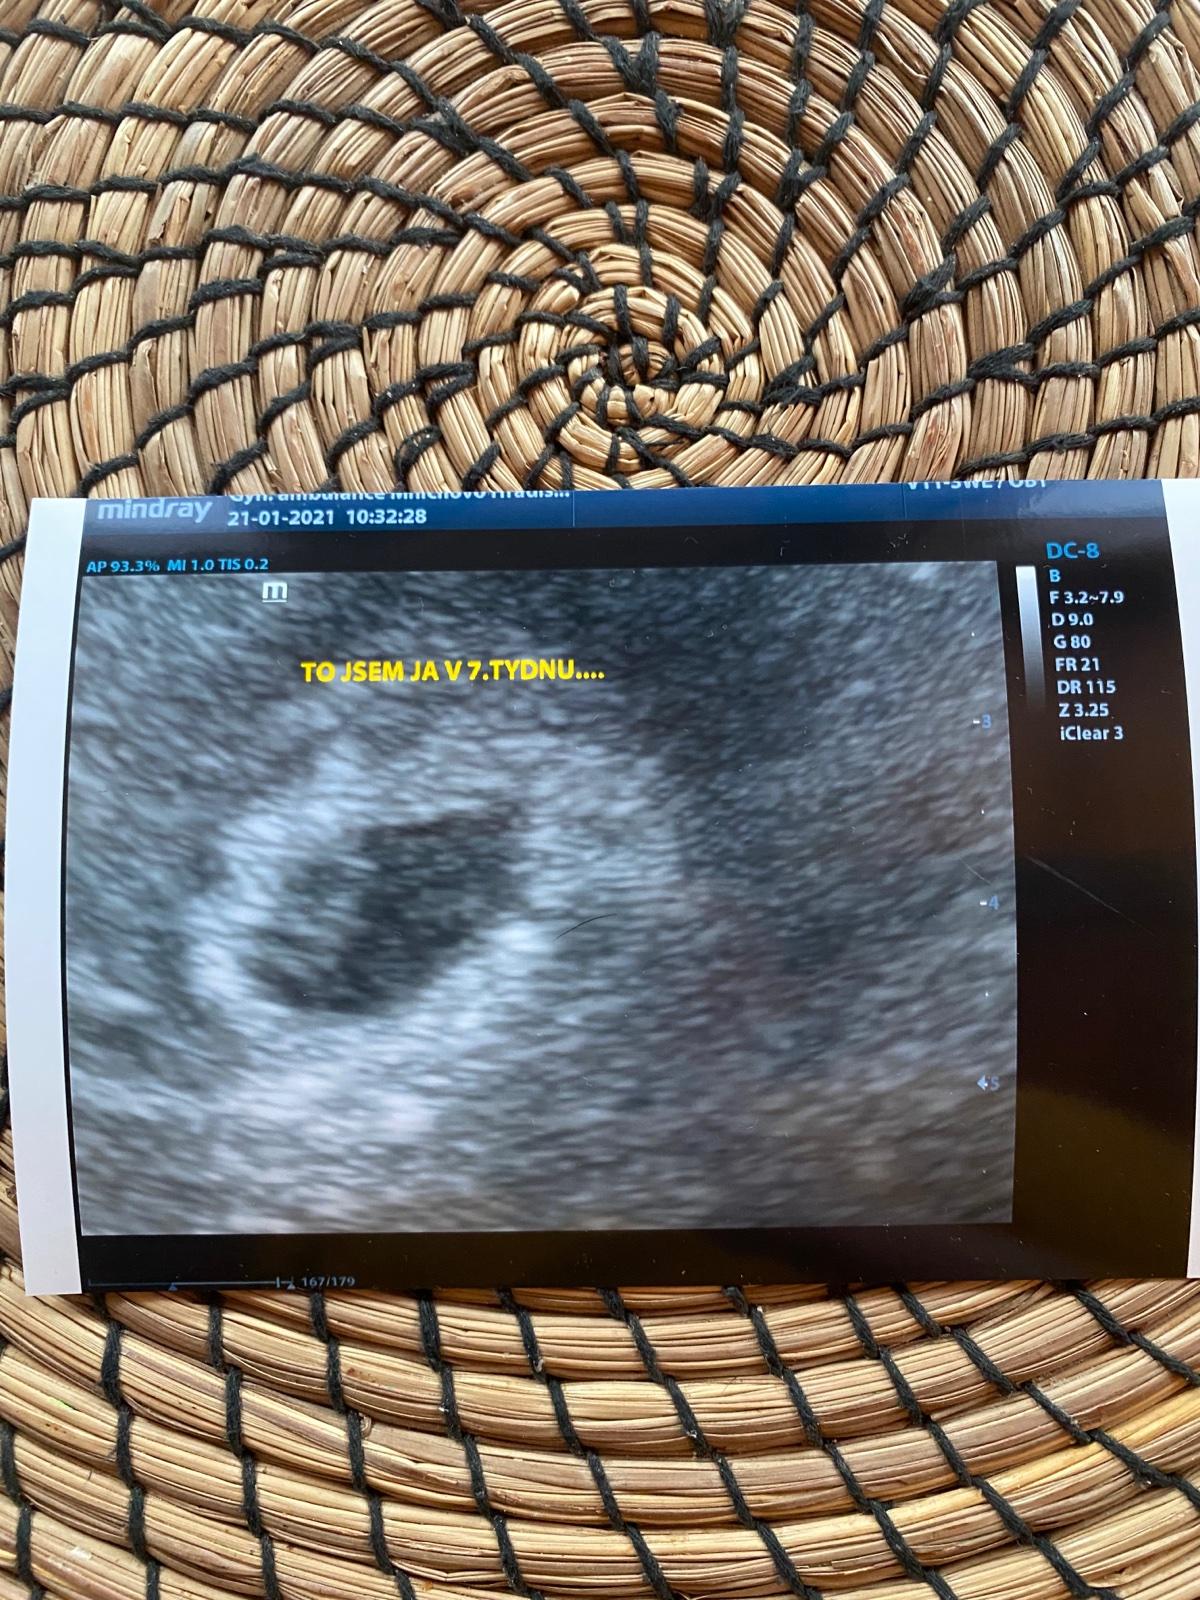

Děvčata dnes jsem byla na kontrole. A vše v pořádku🥰 miminko je tam kde má být🤗 tluče i srdíčko❤️